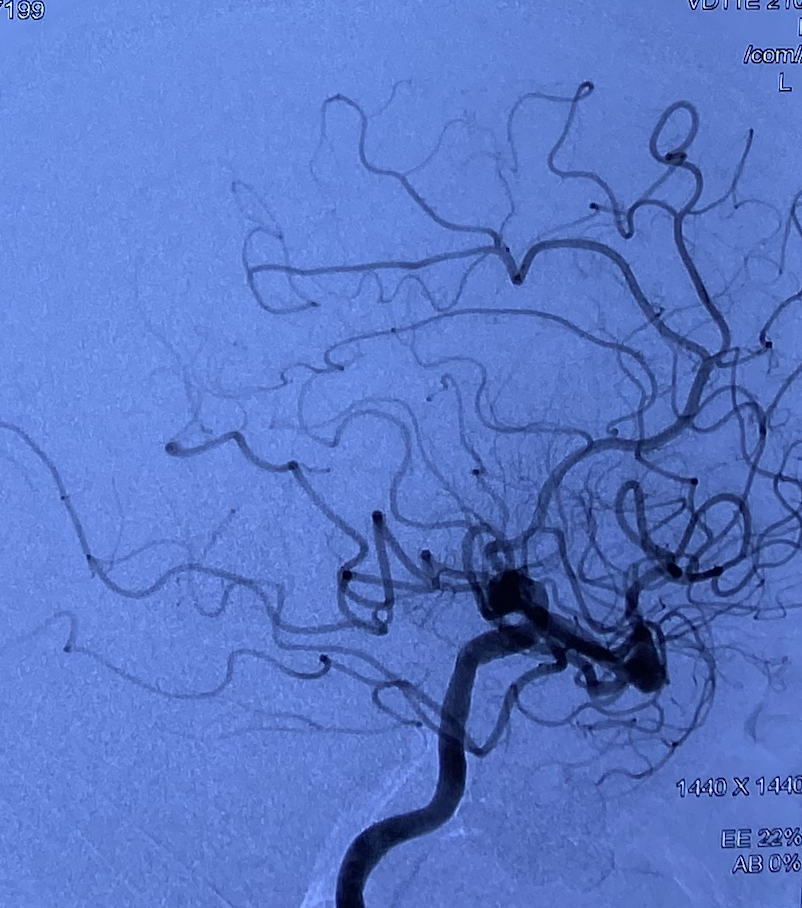

DSA:右侧大脑中动脉瘤,形态不规则,夹层可能,瘤体可见分支血管,4.5mm×3.2mm,瘤颈5.8mm;远近端载瘤动脉直径分别为2.71mm、2.93mm。

畅医达(Choydar)FD输送到位,调整合适位置后逐渐释放‍。

术后正侧位造影片提示颅内血管显影良好,支架打开充分,瘤颈处推密,贴壁良好,动脉瘤内造影剂滞留明显。